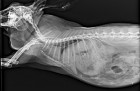

Ez a képalkotó diagnosztikai eljárás különösen fontos a nyuszik gyógyászatában, hiszen a fizikai betegvizsgálatot kiegészítve alkalmas többek között a rájuk igencsak jellemző fogászati megbetegedések és emésztőrendszeri problémák (pl. bélelzáródás) pontos(abb) diagnosztizálására.

Amennyiben szükséges, első lépésben általában röntgenfelvétel szokott készülni a nyusziról (tehát még UH, CT vagy MRI vizsgálatot megelőzően).

Miután elkészült a röntgen, állatorvosa azonnal ki is tudja azt értékelni: ki tud zárni bizonyos betegségeket, fel tudja állítani a pontos diagnózist, elő tudja írni a szükséges kezelést (pl. gyógyszer, műtéti eljárás), vagy esetleg az ott látottak alapján dönt további szükséges diagnosztikai lépésekről (pl. kiegészítő UH lesz szükséges).